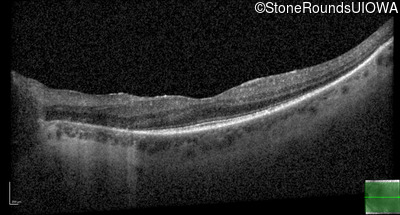

OCT Stack

20/32

20/32 -1

20/30 -2

20/32 -2

20/40

20/25 sc